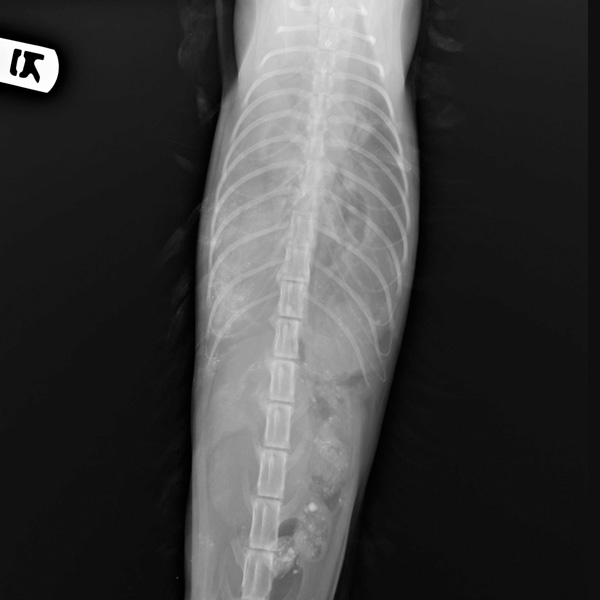

پارگی دیافراگم

نام حیوان :

ملوس

تاریخ امداد :

2020-08-27

منطقه :

نارمک

هزینه تقریبی :

۲ میلیون تومان

حامی :

پت شاپ شاپرک